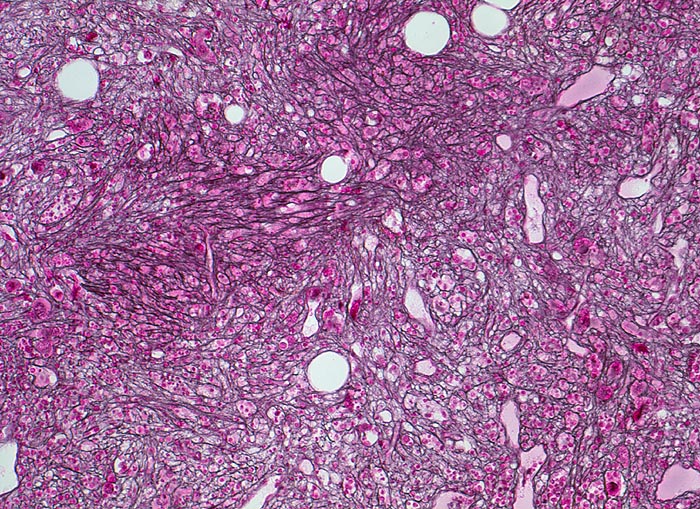

• Kollagenfibrose.

• Dilatierte Sinusoide mit intrasinusoidaler Blutbildung.

• Retikulinfaserfibrose des Marks vorhanden aber in der HE Färbung schwierig quantifizierbar.